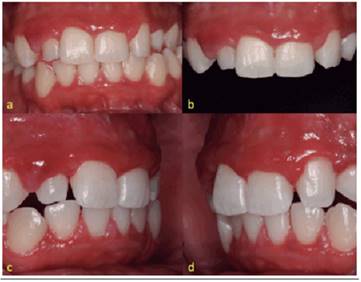

The patient presented regression of gingival growth and no bleeding after the first weeks of local and systemic treatment. The maxillary and mandibular teeth presented their crowns intact and without mobility after an interval of two months. Maintenance appointments occurred every fortnight in the first semester of treatment and every 30 days from the second semester, when deplacement procedures and oral hygiene instructions were performed (Figure 3a, 3b, 3c, 3d).